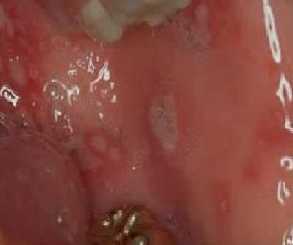

白塞病早期症状,白塞病的症状

白塞病的临床表现,你知道多少?

白塞氏病是一种全身性的,慢性血管炎疾病,常常伴随的症状表现就是口腔

反复口腔溃疡,需警惕是白塞病

白塞病的症状

白塞病口腔溃疡